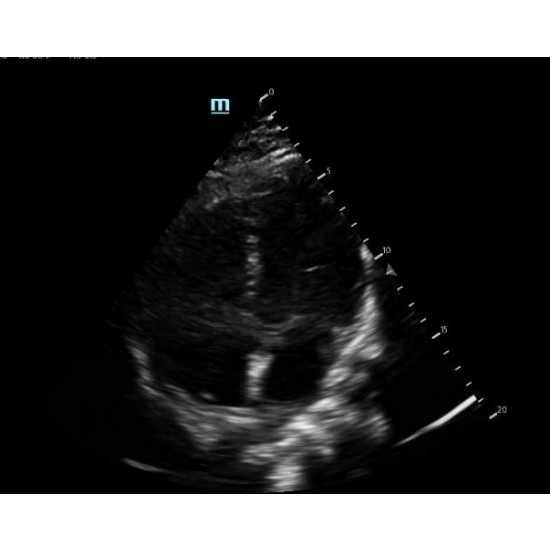

| The Sign Of Levine, But What Does It Mean? - Page #3 | |||